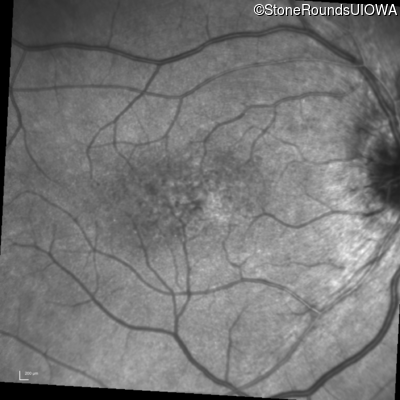

Visit at age: 16 years

Fundus Photography - Right - 20/30 -2

Exemplar